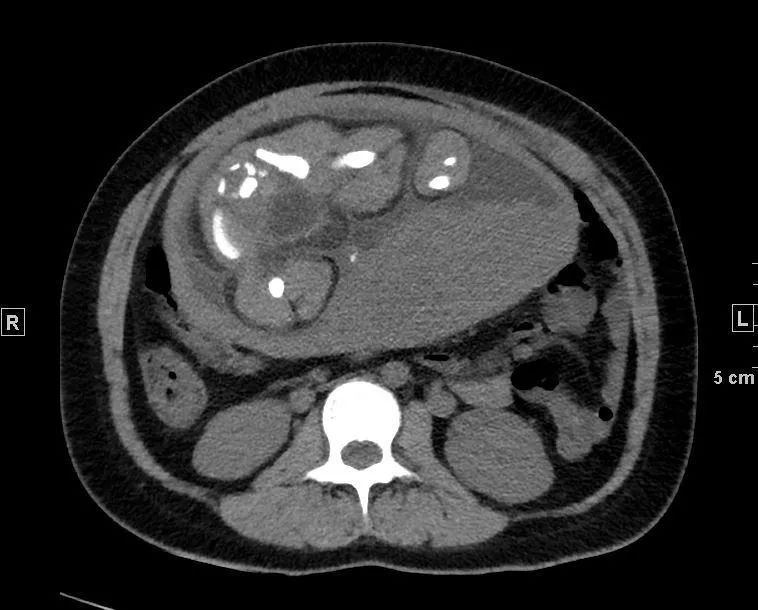

患者的腰椎间盘突出不是严重,之所以将患者家属喊来询问病史,是因为看到了腹主动脉血管壁钙化,确切的说是“不一样”血管壁钙化,腹主动脉(双肾下极水平以下)内分隔影伴钙化(如下图):

正常情况下,老年人血管壁有钙化是再正常不过,但钙化即使再严重,也是呈环形贴着血管壁,上面这样钙化很怪异,分隔伴细条状钙化。如果没有任何症状,可能是正常的;但当有症状时,而且腰痛用正常的腰椎间盘突出难以解释时,不能除外一种相对少见但非常危险的情况——“主动脉夹层”。

还好,那一下午人不不多,很快开申请单、登记、预约,一小时后做了胸腹盆增强CTA,当看到增强图像时,让我们倒吸一口凉气,约L1椎体水平至左侧髂总动脉夹层。患者紧急住院。

腹主动脉CTA腹腔干水平(骨窗) 左侧髂总动脉(骨窗)